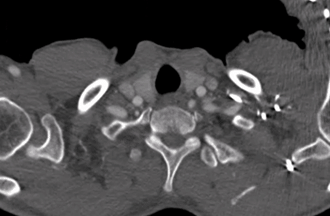

主动脉CTA详解:Standford B型主动脉夹层,破口位于胸降主动脉,破口直径7mm,假腔位于真腔前缘;主动脉管壁周围少许渗出影,可见壁内血肿、血栓、溃疡突起,近端血肿已累及LSA根部,LSA与LCCA距离仅8.5mm,左椎动脉优势;弓上三分支血流显影可,内脏区腹腔干动脉、肠系膜上动脉及右肾动脉起自假腔,左肾动脉起自真腔。

主动脉管壁壁内血肿已累及LSA根部,近端锚定区明显不足, 且LCCA距离LSA不足10mm,需向近端扩展锚定区,重建LSA。

LSA与主动脉弓成锐角,且开口处粗大,呈“火山口”形态,为术中原位开窗角度控制带来难点,且市面常见覆膜支架,开窗难度较大。